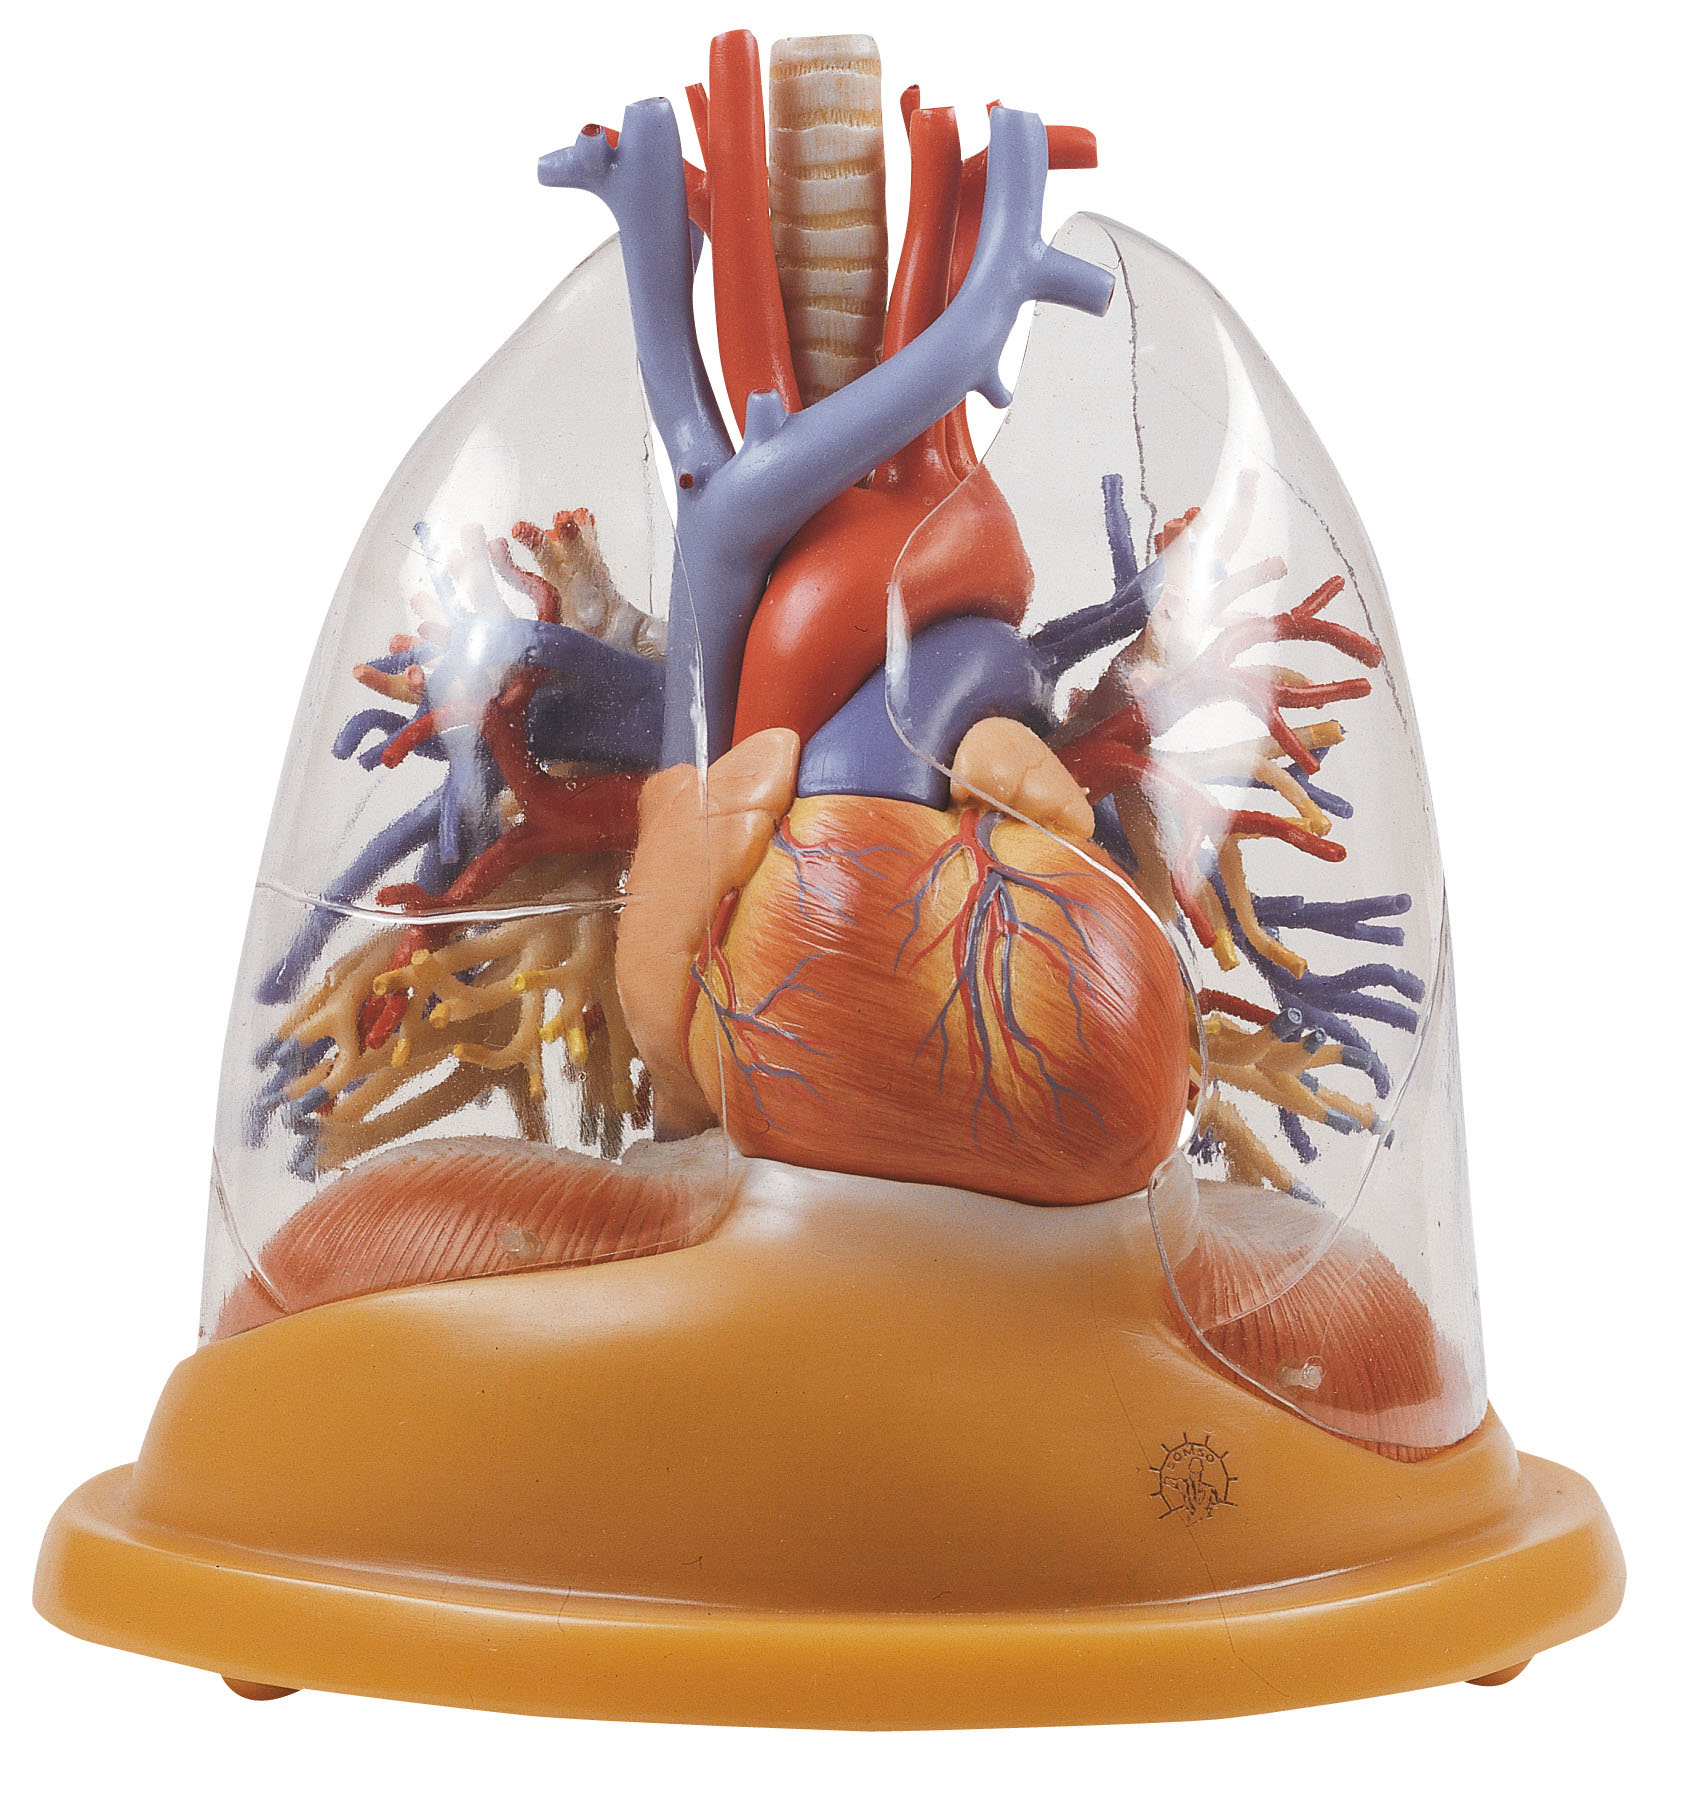

Lungs With Heart, Diaphragm and Larynx

- ¾ natural size, in SOMSO-PLAST®

- The model shows the viscera of the thorax

- Bifurcation of the trachea and oesophageal hiatus with aortic hiatus in the diaphragm is demonstrated